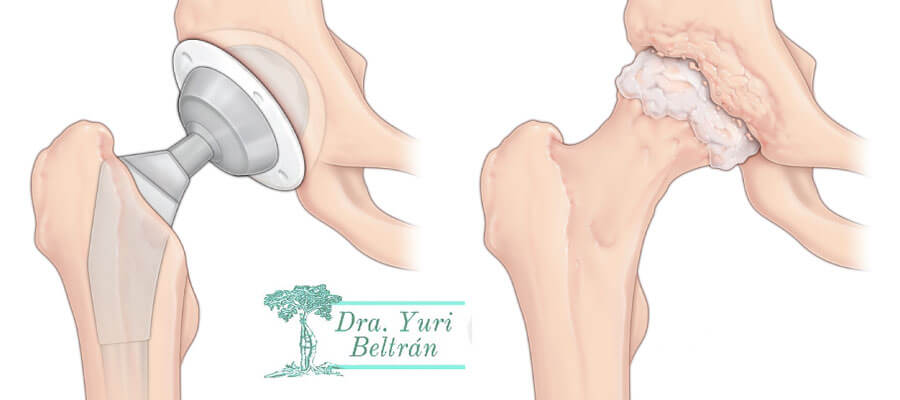

El reemplazo total de cadera es la cirugía de cadera más común. Utiliza componentes artificiales para reemplazar toda la estructura de la cadera. Durante el procedimiento, los cirujanos insertan un vástago en el fémur o el hueso del muslo del paciente para darle estabilidad. Reemplazan la cabeza del fémur con una bola y reemplazan la cavidad natural de la articulación de la cadera con una copa artificial.

Prótesis Parcial de Cadera

El reemplazo parcial de cadera remueve y reemplaza la cabeza del fémur del paciente, que es la bola en la parte superior del fémur, o hueso del muslo. No reemplaza el encaje. Una bola de cerámica o de metal se adjunta a la parte superior de un vástago que se inserta en el centro hueco del fémur. Los cirujanos suelen realizar esta cirugía para reparar ciertos tipos de fracturas de cadera.